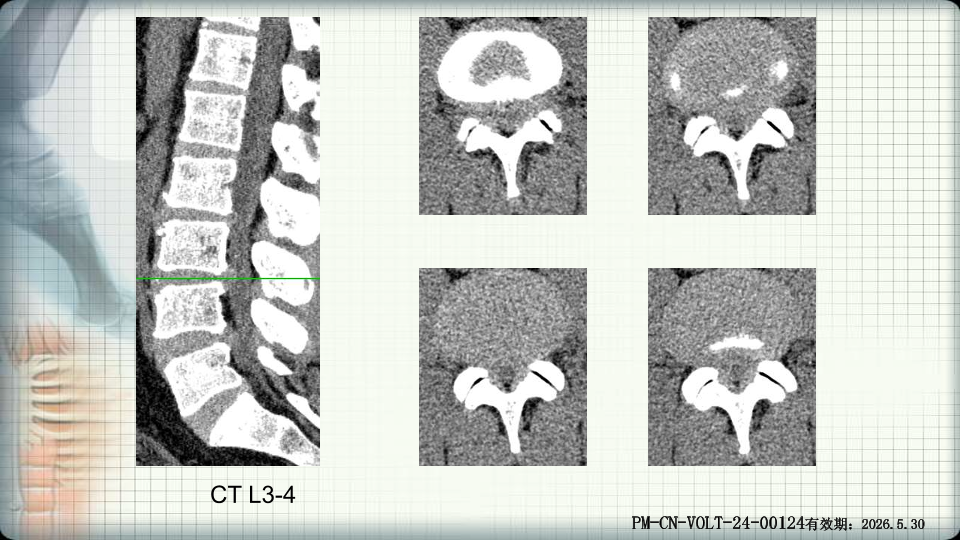

管狭窄症非手术治疗-谢学虎